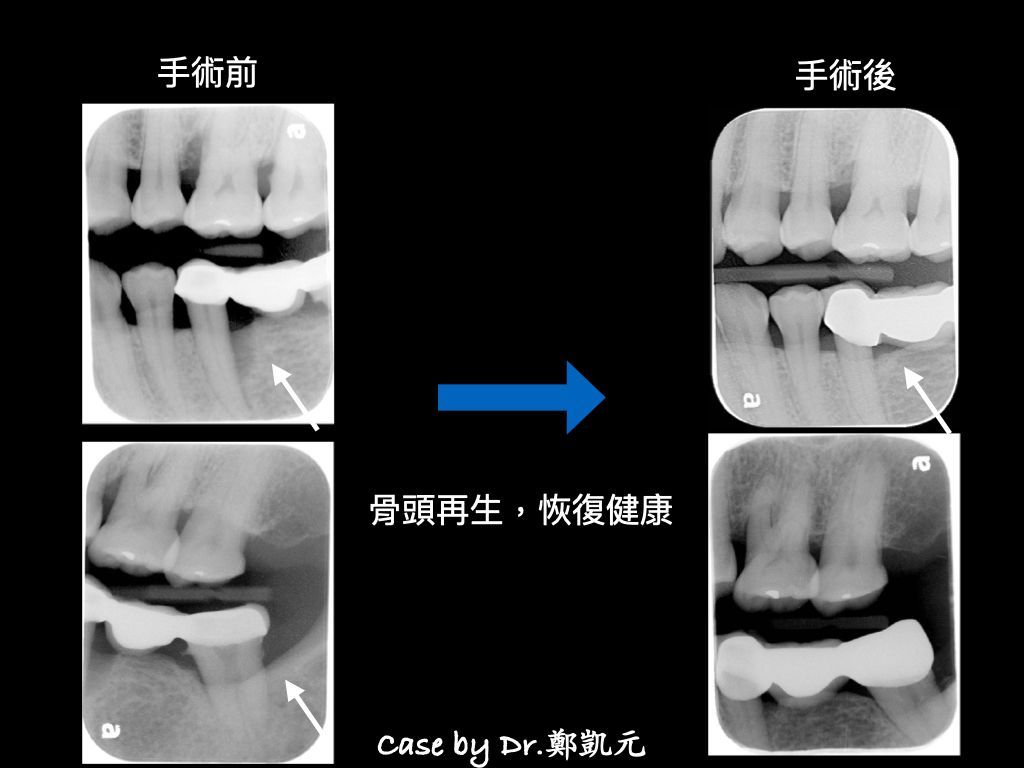

牙周再生手術

放入骨粉、再生膜/再生膠,幫助自體骨頭生長癒合,恢復牙周健康